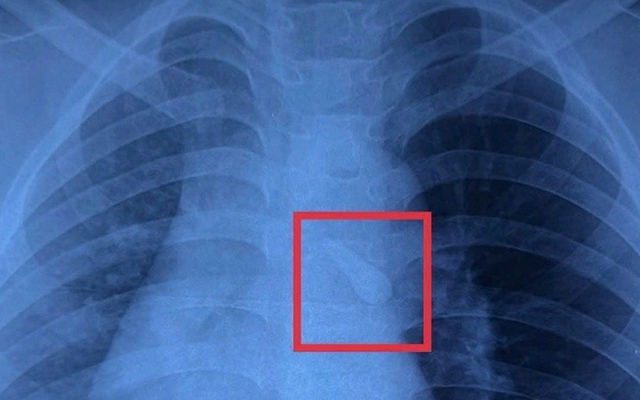

Kết quả chụp X-quang ghi nhận dị vật cản quang trong khí quản. Khai thác bệnh sử cho thấy trẻ bị mất răng số 21 sau tai nạn, các bác sĩ nghi ngờ răng đã bị hít sặc vào đường thở. Trẻ được chẩn đoán đa chấn thương, trong đó có dị vật đường thở, và được hội chẩn liên chuyên khoa Ngoại thần kinh, Ngoại tổng hợp, Mắt, Răng hàm mặt và Tai mũi họng.

Trước nguy cơ tắc nghẽn đường thở và biến chứng hô hấp, bệnh nhi được chỉ định nội soi can thiệp khẩn cấp. Ca phẫu thuật do TS.BS Phú Quốc Việt, Phó khoa Tai mũi họng Bệnh viện Nhi đồng 1, thực hiện với sự phối hợp của ekip gây mê - hồi sức. Qua nội soi, ê kíp phát hiện chiếc răng nằm tại carina khí quản và gắp ra thành công.